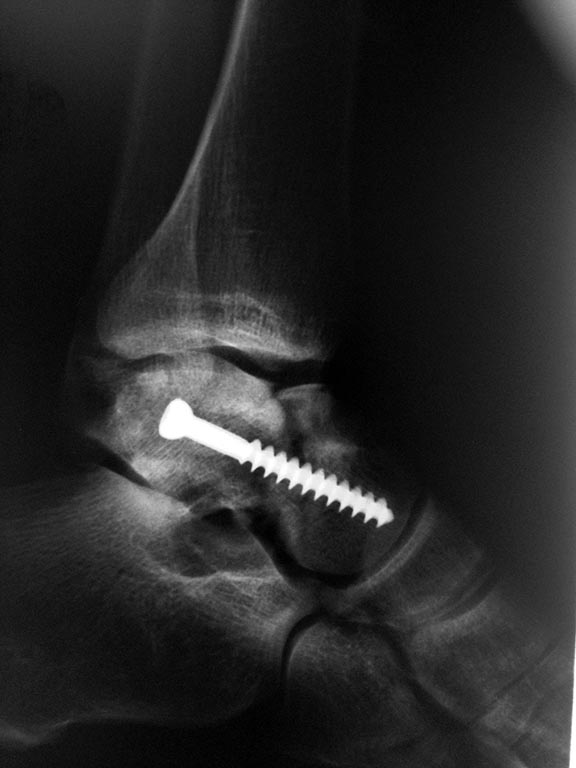

Артроскопический остеосинтез таранной кости

Доступ стандартный задний. Сначала визуализированы задний отдел голеностопного и подтаранного суставов, удалены осколки. Далее под контролем ЭОПа проведена направляющая спица, высверлен канал и вкручен спонгиозный винт.

Рентгенограммы после операции

После операции месяц находился в гипсе, ниже рентгенограммы через месяц

Имеются явные признаки консолидации, гипс снят. По-моему прикольно, вместо такой большой операции все делать артроскопически. При этом кровоснабжение таранной кости не нарушается, риск асептического некроза минимизируется.